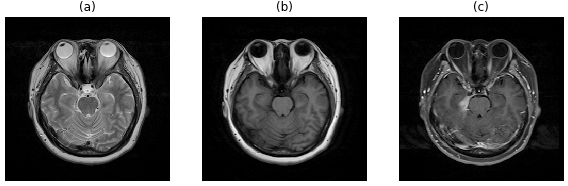

As introduced earlier, the encoder in the AIRNet is able to extract a generalised representation of different image modalities. Three modalities used in this study are T2-weighted, T1-weighted and contrast-enhanced T1-weighted (Fig. 3). Although pixel intensities of the same brain tissue can vary in different modalities, the encoder can capture general features across modalities. The selection of most discriminative features, which concisely describe complex morphological patterns of the brain, addresses the concern of the registration method not being able to scale well to various image modalities. To test the effectiveness of our encoder, three training datasets were prepared: